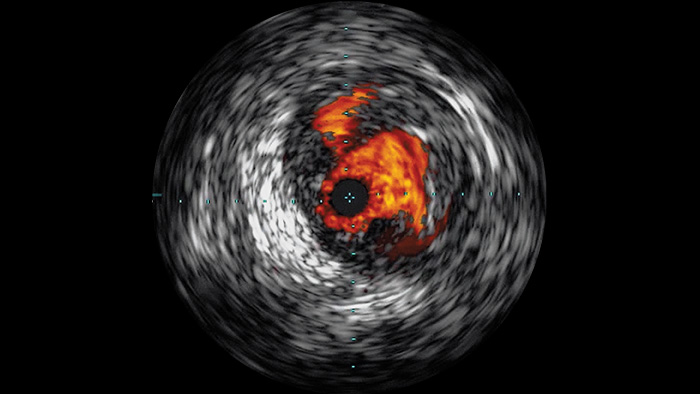

血管内超音波検査(IVUS)はカテーテルベースのイメージング技術であり、これを利用して医師は内部から血管を視覚化して、疾患の有無と程度を評価することができます。IVUSは、患者ごとに適切なインターベンション治療の選択、支援、そして確証に役立ちます。

血管の高精細画像は血管の細部まで鮮やかに捉えるため、正確な治療戦略、ナビゲーション、フォローアップをサポートします。